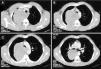

En las imágenes de tomografía computarizada se observa en el mediastino medio una gran masa de 12×9,7cm, heterogénea, de bordes bien definidos y con áreas hipodensas en su interior (A). La lesión comprime y desplaza hacia la izquierda la tráquea (B y C) y se extiende hasta la salida del bronquio superior derecho, desplazándolo y comprimiendo la salida del bronquio y del parénquima del lóbulo superior derecho (D).

Varón de 50 años, fumador, que en el año 2004 había sido diagnosticado de un DFSP de 7cm de diámetro localizado en la región escapulohumeral izquierda. El tratamiento inicial fue quirúrgico, pero tras la resección los bordes profundos se encontraban afectos. El paciente sufrió varias recidivas locales tratadas quirúrgicamente en 2006 y en 2009. En la última biopsia quirúrgica los bordes estaban libres de tumor y el paciente no recibió ningún tratamiento adyuvante. Últimamente consultó por fiebre, artralgias y tos no productiva. La radiografía mostraba una masa paratraqueal. En la TC se confirmaba la presencia de una masa mediastínica heterogénea con compresión de estructuras adyacentes (fig. 1). En la fibrobroncoscopia se objetivó una mucosa edematosa en la entrada del bronquio principal y del lóbulo superior derecho. Se hizo una PTT ciega con una aguja histológica MW-319 (Bard-Wang, Billerica, Massachusetts, EE. UU.) y el resultado anatomopatológico fue de metástasis de DFSP, basado en la morfología de las biopsias y apoyado por técnicas de inmunohistoquímica (fuerte expresión de vimentina y CD34) y por el estudio genético-molecular (presencia de translocación de cromosomas 17 y 22).